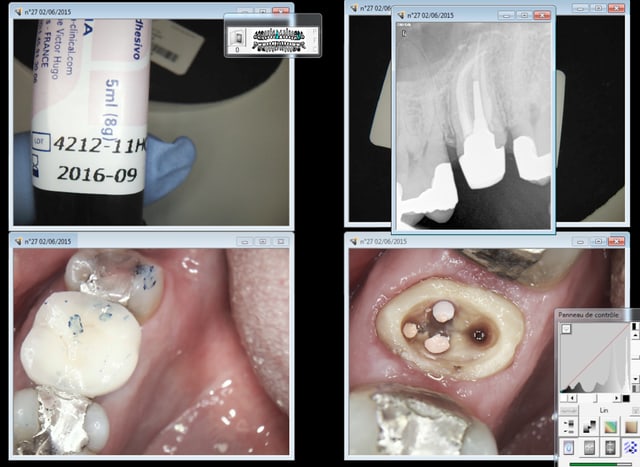

Comme ca ? -)))))

Capture d e cran 2015 06 02 16.26 - Eugenol